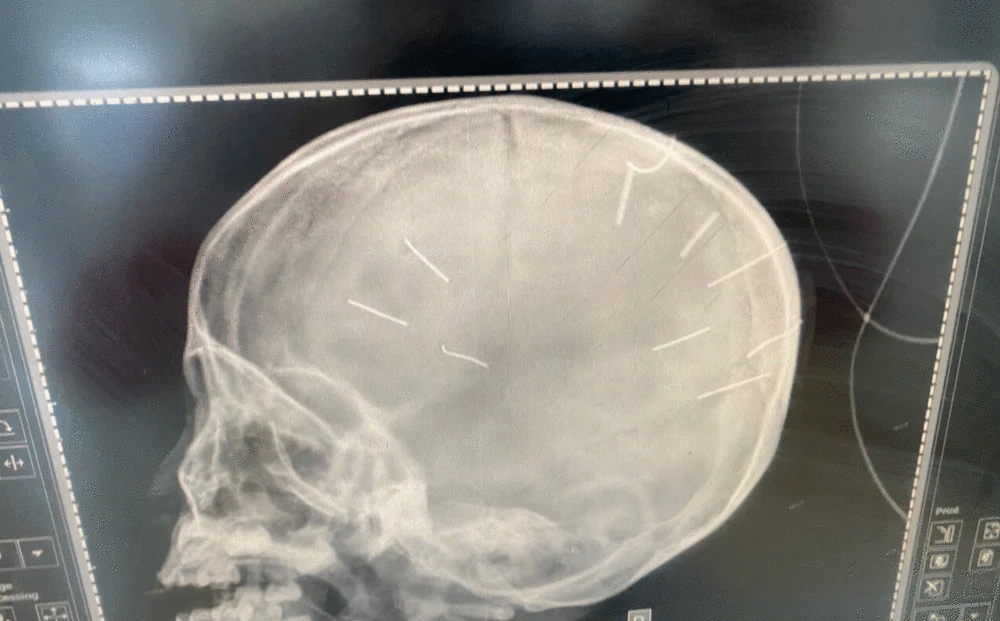

| Hình ảnh chụp X-quang hộp sọ bệnh nhân với 9 hình thể như bị đinh bắn vào. |